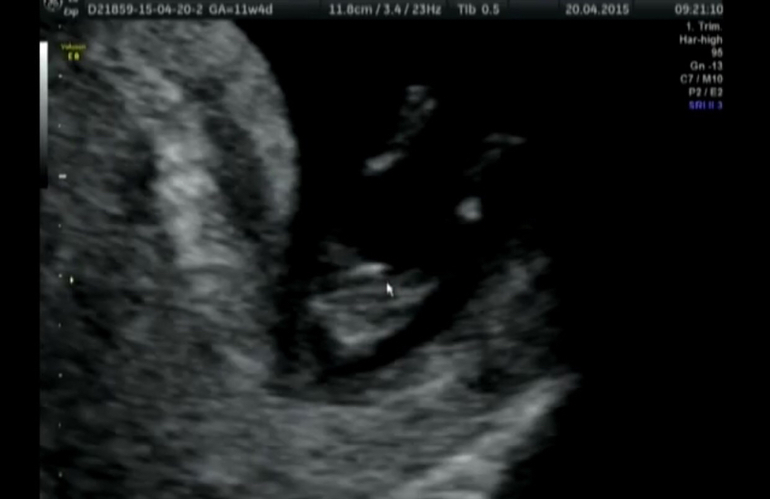

Узи сделано в 11 недель и 5 дней.

На бугорок указывает курсор, ножки у нас растопырки 😂 ракурс снизу (попка и ножки). Ниже другой ракурс